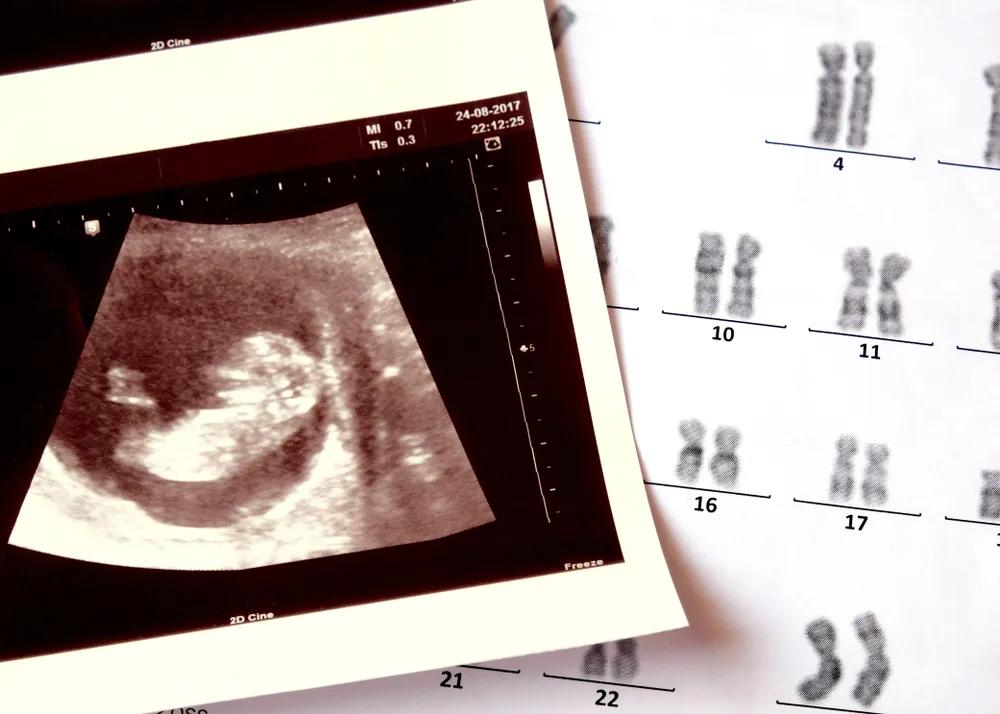

很多生育障碍的夫妇,寄希望于试管等生殖技术,来改变生活状态,但技术的不确定,让焦虑卷土重来,很多女性被身体受创与生殖焦虑反复拉扯。

曾纪琪夫妇正在尝试试管婴儿。

为了尽可能排除那一点点因素,曾纪琪和黎晓都选了更明确的方案 —— 试管。

曾纪琪决定做试管之后,开始进入各种各样的试管群和求子论坛和不同的人聊天,她看到群里有不少人经历过四五次的、甚至有十几次还没有成功的,很多人是从安徽、苏北一些县和农村来到南京租房子做试管,最低费用的一代试管,一次也需要 4~5 万,很多人举债十几万仍未成功,她想给自己打个心理上的预防针。